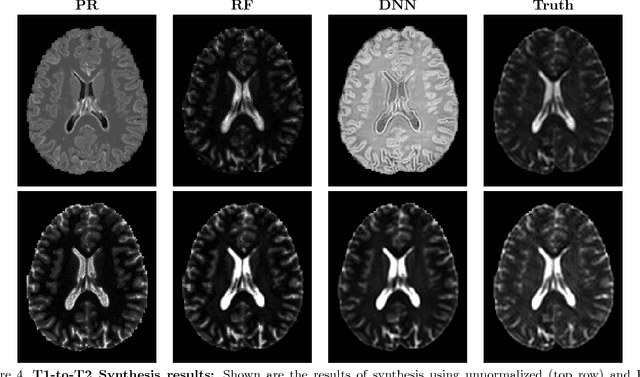

Image synthesis learns a transformation from the intensity features of an input image to yield a different tissue contrast of the output image. This process has been shown to have application in many medical image analysis tasks including imputation, registration, and segmentation. To carry out synthesis, the intensities of the input images are typically scaled--i.e., normalized--both in training to learn the transformation and in testing when applying the transformation, but it is not presently known what type of input scaling is optimal. In this paper, we consider seven different intensity normalization algorithms and three different synthesis methods to evaluate the impact of normalization. Our experiments demonstrate that intensity normalization as a preprocessing step improves the synthesis results across all investigated synthesis algorithms. Furthermore, we show evidence that suggests intensity normalization is vital for successful deep learning-based MR image synthesis.